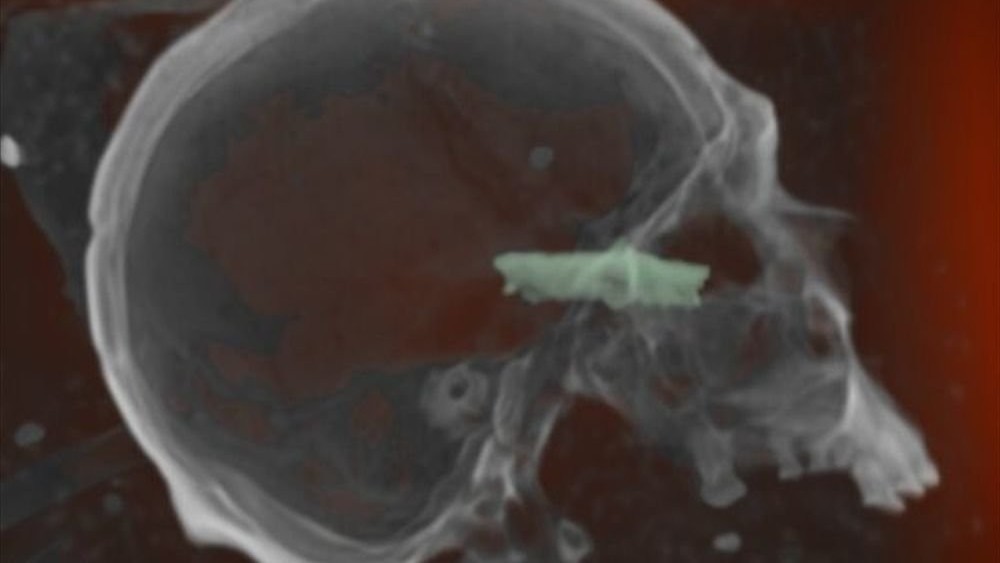

| Обнаруженные пять лет назад мумии на территории археологического памятника Пачакамак были изучены при помощи мобильного рентгеновского комплекса учёными из Университета Западного Онтарио (Канада). Всего было просканировано 200 останков, датированных 1100-1470 годами. На многих снимках учёные заметили странные артефакты, сообщает портал WWW.PLANETANOVOSTI.COM. Всего было сделано 880 снимков и проведено 31 компьютерное сканирование. Позже из двухмерных снимков создали некую мозаику, объединив их вместе для получения четкой цифровой картинки. Как выяснилось, многие тела сохранились частично, поэтому сних нельзя было снимать слой ткани. На одном снимке специалисты увидели согнутый диск, названный «тако». На другом – острый предмет, который застрял в глазнице одной из мумий. На третьем снимке все рассмотрели татуировку на руке и большое количество хлопковых семян, которые требовались, скорее всего, для проведения погребального ритуала. Неизвестно, были ли мумифицированы тела. Возможно, они сами дошли до такого состояния вследствие сухого климата. Также остается открытым вопрос, при каких обстоятельствах все предметы появились в телах умерших. |